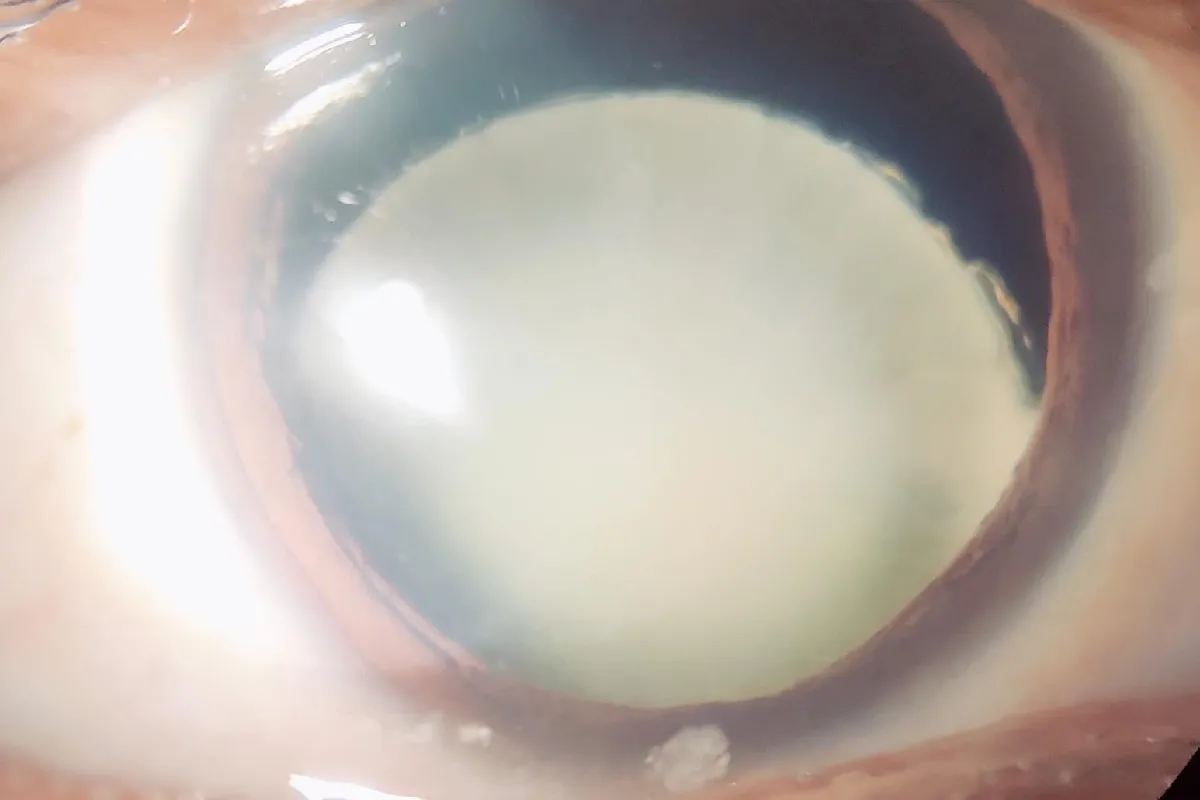

We handle complex cataract cases including mature cataracts, post-traumatic cataracts, subluxated lenses, and cataracts with associated ocular conditions. Our approach ensures optimal outcomes with enhanced visual recovery.